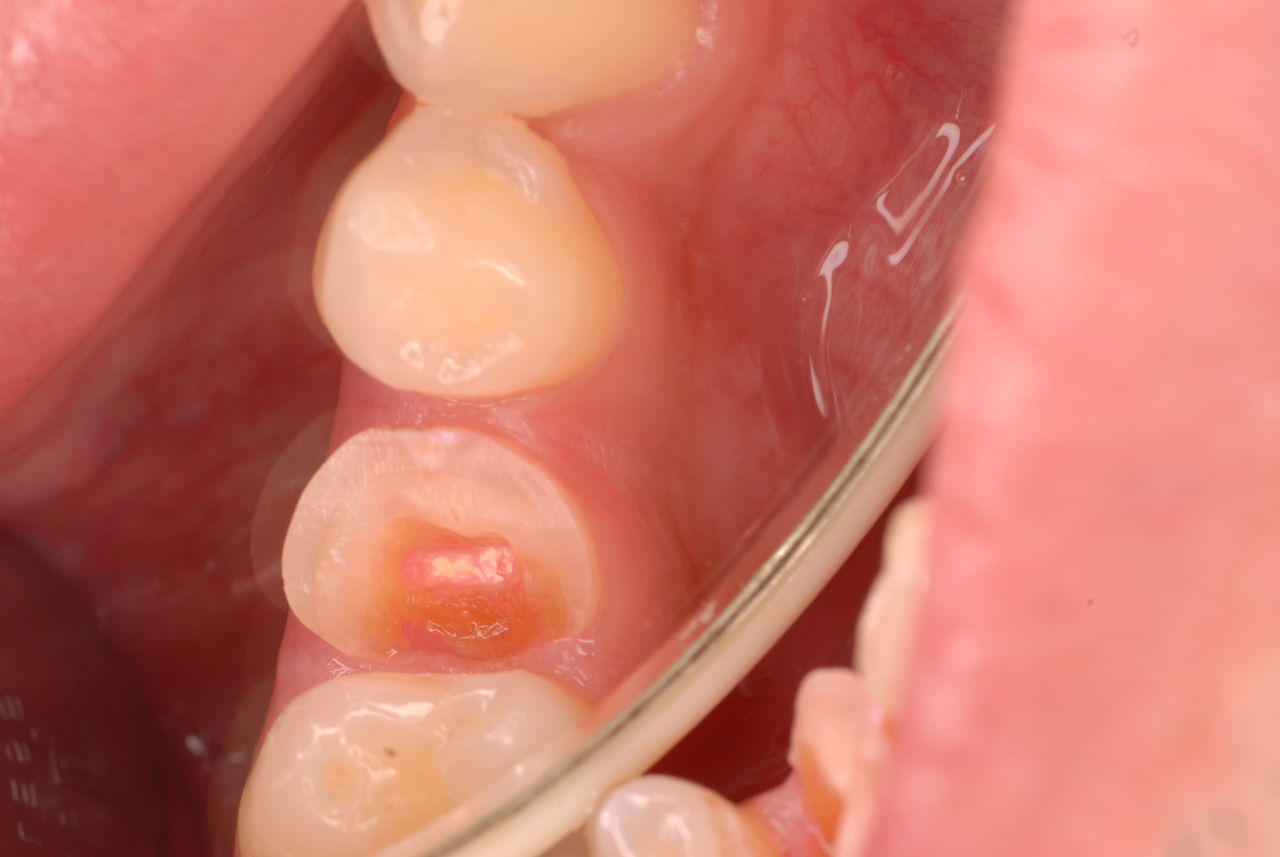

30代の男性の方です。

入れ歯を入れていました。歯科医院で歯を抜けず仕方なく入れ歯にしたとか。何とかならないものだったのか悔やまれました。

抜いた歯はありません。

一応差し歯にしましたが、歯茎の状態はよくはありません。

とりあえず希望を入れて差し歯にしたような感じです。